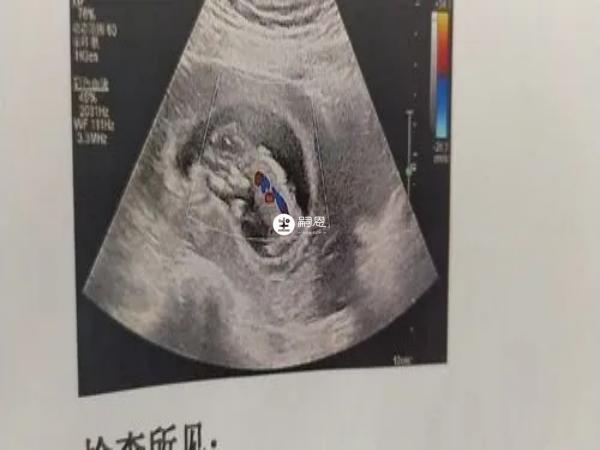

判斷出卵泡質量的好壞,最簡單的方法就是到醫院做超聲檢查,最好在月經第2天或是第3天進行檢查,此時能夠看到卵泡的發育大小和形態,就能瞭解發育情況。